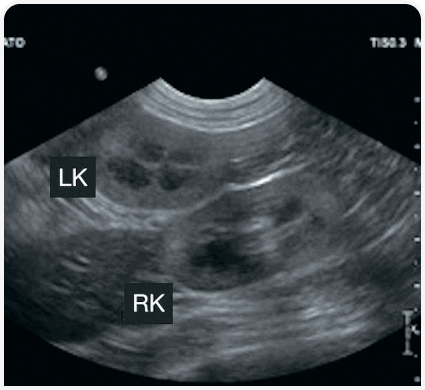

Ранняя диагностика хронической болезни почек

Пациент: Луна, кошка, 8 лет

Жалобы: Отсутствуют. Обращение на плановый профилактический осмотр. При пальпации — небольшая плотность почек.

Диагноз: УЗИ брюшной полости выявило снижение размеров и неоднородность паренхимы почек — признаки хронической болезни почек на ранней стадии (IRIS Stage 1–2). Лабораторно подтверждено повышение SDMA, креатинин в верхней границе нормы.

Что дало УЗИ: УЗИ позволило выявить структурные изменения до появления клинических признаков, что дало возможность начать коррекцию питания и назначить нефропротективные препараты.

Результат: Через 9 месяцев контроля — стабильные лабораторные показатели, отсутствие прогрессирования. Луна сохраняет отличное качество жизни.